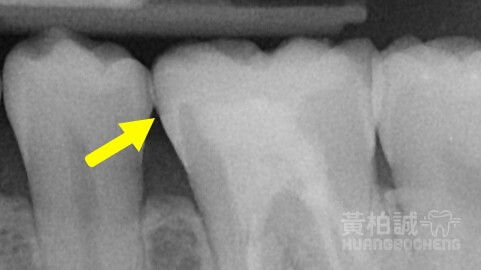

嵌體俗稱3D齒雕,是保存後牙齒質最高極致的修復後牙的方式。

跟傳統牙冠相比,它比較像半罩式安全帽,但保護牙齒避免斷裂的效果卻比傳統牙冠一樣(甚至更勝一籌)

一個完美的3D齒雕應該要看起來與患者的牙齒會是嚴絲合縫的狀態,密合到幾乎看不出任何接隙存在的。

只有這樣嚴絲合縫的品質才能讓患者使用長長久久、不粗糙刮舌、並且大幅避免未來齒質再次崩壞的機率。